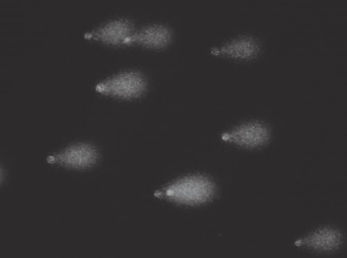

The comet assay also known as single cell gel electrophoresis in vitro bioassay is widely used for pharmaceutics, medical and screening assessments.

The comet assay as an indicator test for negative effects to the genome of human cells evaluates the cancer risk of mixtures or single components by measuring the destruction of the DNA of each cell in form of a comet before a mutation takes place.